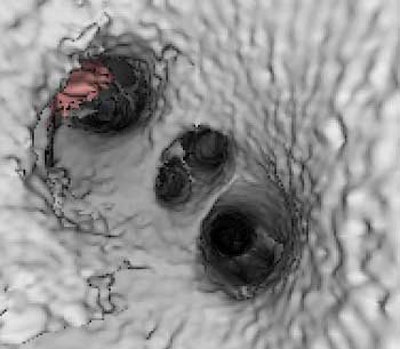

![]() |

| Endocardial (above) and epicardial (below) views from a patient with an accessory vein on the right (which happened to be vein that drained the right middle lobe (RML) and superior segment right-lower lobe (ssRLL), as well as separate LS and LI veins (left side seen in epicardial view only), for a total of five pulmonary veins. Images courtesy of Dr. Joan Lacomis. |

Endocardial volume-rendered views of the right and left pulmonary inflow vestibules show the imaging volume from the intra-atrial perspective. They are useful for assessing global size, the shape and volume of the left atrium, the number of veins, accessory veins, and conjoined veins, and for examining the ostial branches and their intravenous saddles, the region of the atrial wall interposed between separate ipsilateral pulmonary veins.

"The electrophysiologists like it because it gives them kind of a global look at endocardial anatomy," she said.